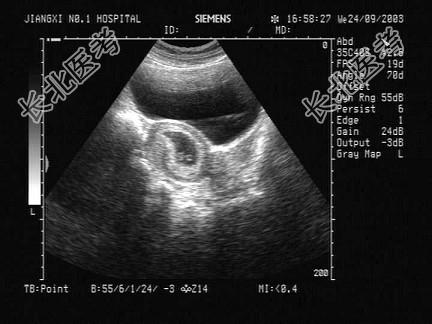

- 单项选择题女性,32岁, 停经45天,B超检查如图, 以下最可能的诊断为 ( )

A、宫腔积液

B、子宫粘膜下肌瘤

C、宫体肌瘤

D、早期妊娠

E、卵巢囊肿